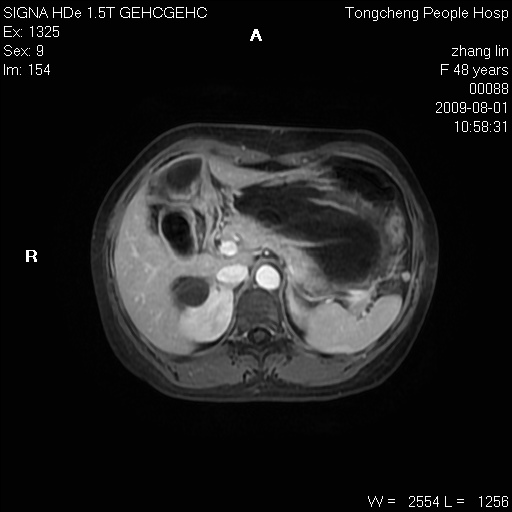

女,48岁。健康体检,彩超发现右肾占位性病变。平素健康。

临床诊断:右肾占位性病变,性质待定(囊肿?肿瘤?)。

上中腹部mr平扫+增强扫描,图像如下:

右肾上极见一类圆形病灶,t1wi呈等信号t2wi呈等高混杂信号,三期增强无强化,边界清---考虑囊肿出血。

同反相位均表现为等信号,病变无强化,考虑含蛋白的囊肿可能,弥散加权相或许有些帮助,

慢性胆囊炎